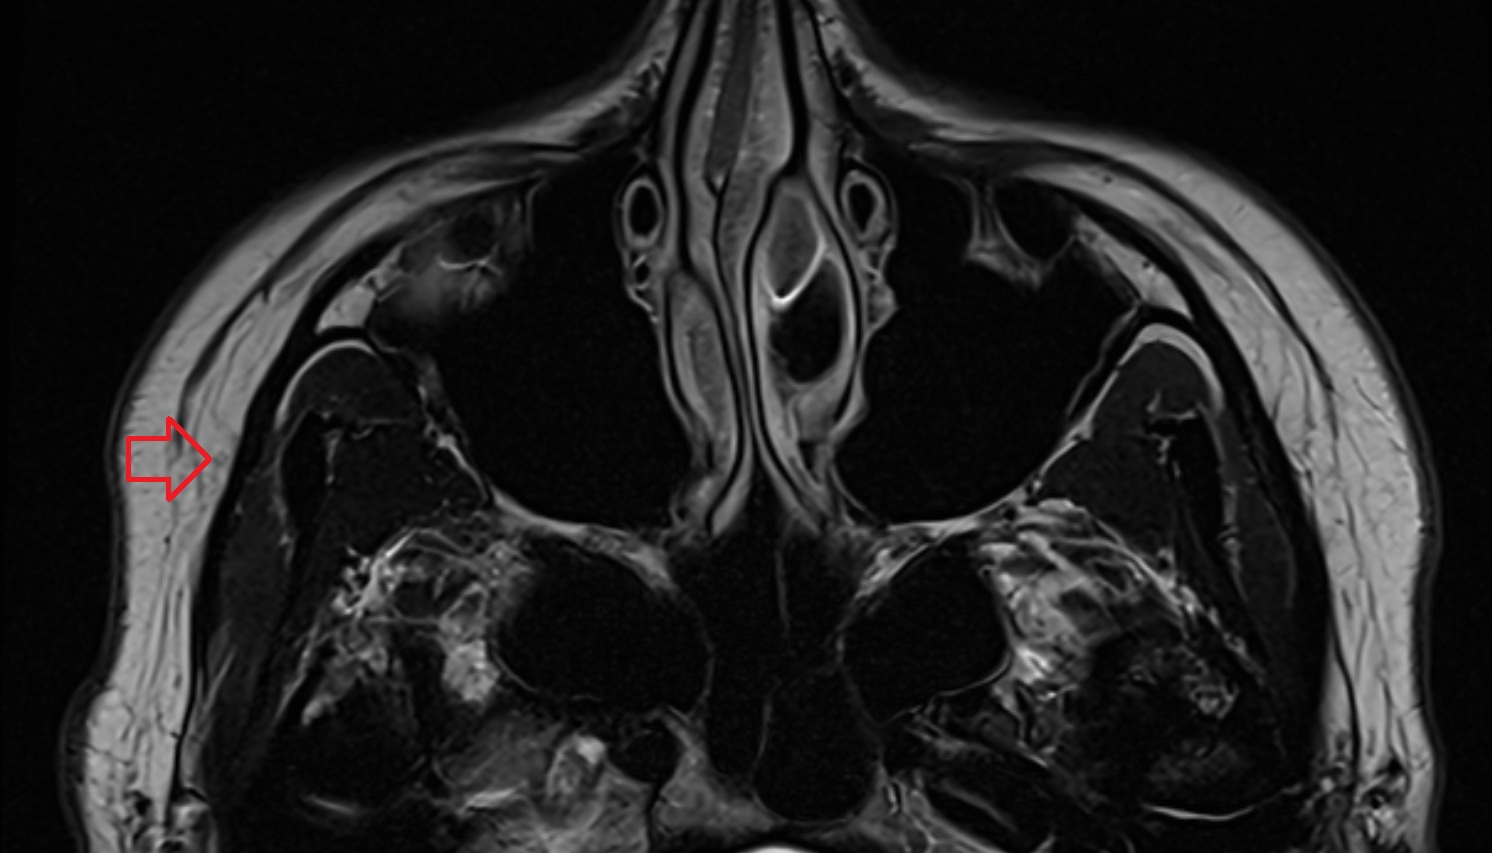

- Temporomandibular joint

- Mandibular condyle

- Mandibular fossa

- Mastoid process

- Petrous part of temporal bone

- Squamous part of temporal bone

- Zygomatic process of temporal bone

- Deep part of masseter muscle

- Superficial part of masseter

- Superior head of lateral pterygoid muscle

- Inferior head of lateral pterygoid muscle

- Lateral pterygoid muscle

- Masseter muscle

- Temporalis muscle